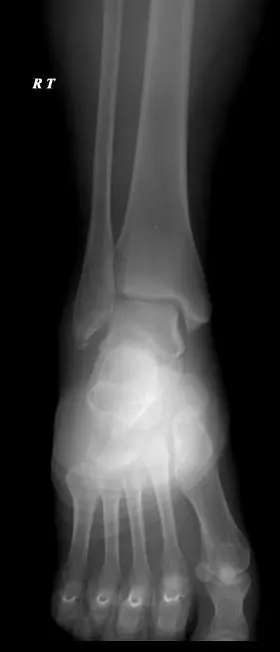

Cheville

Fractures malleolaires